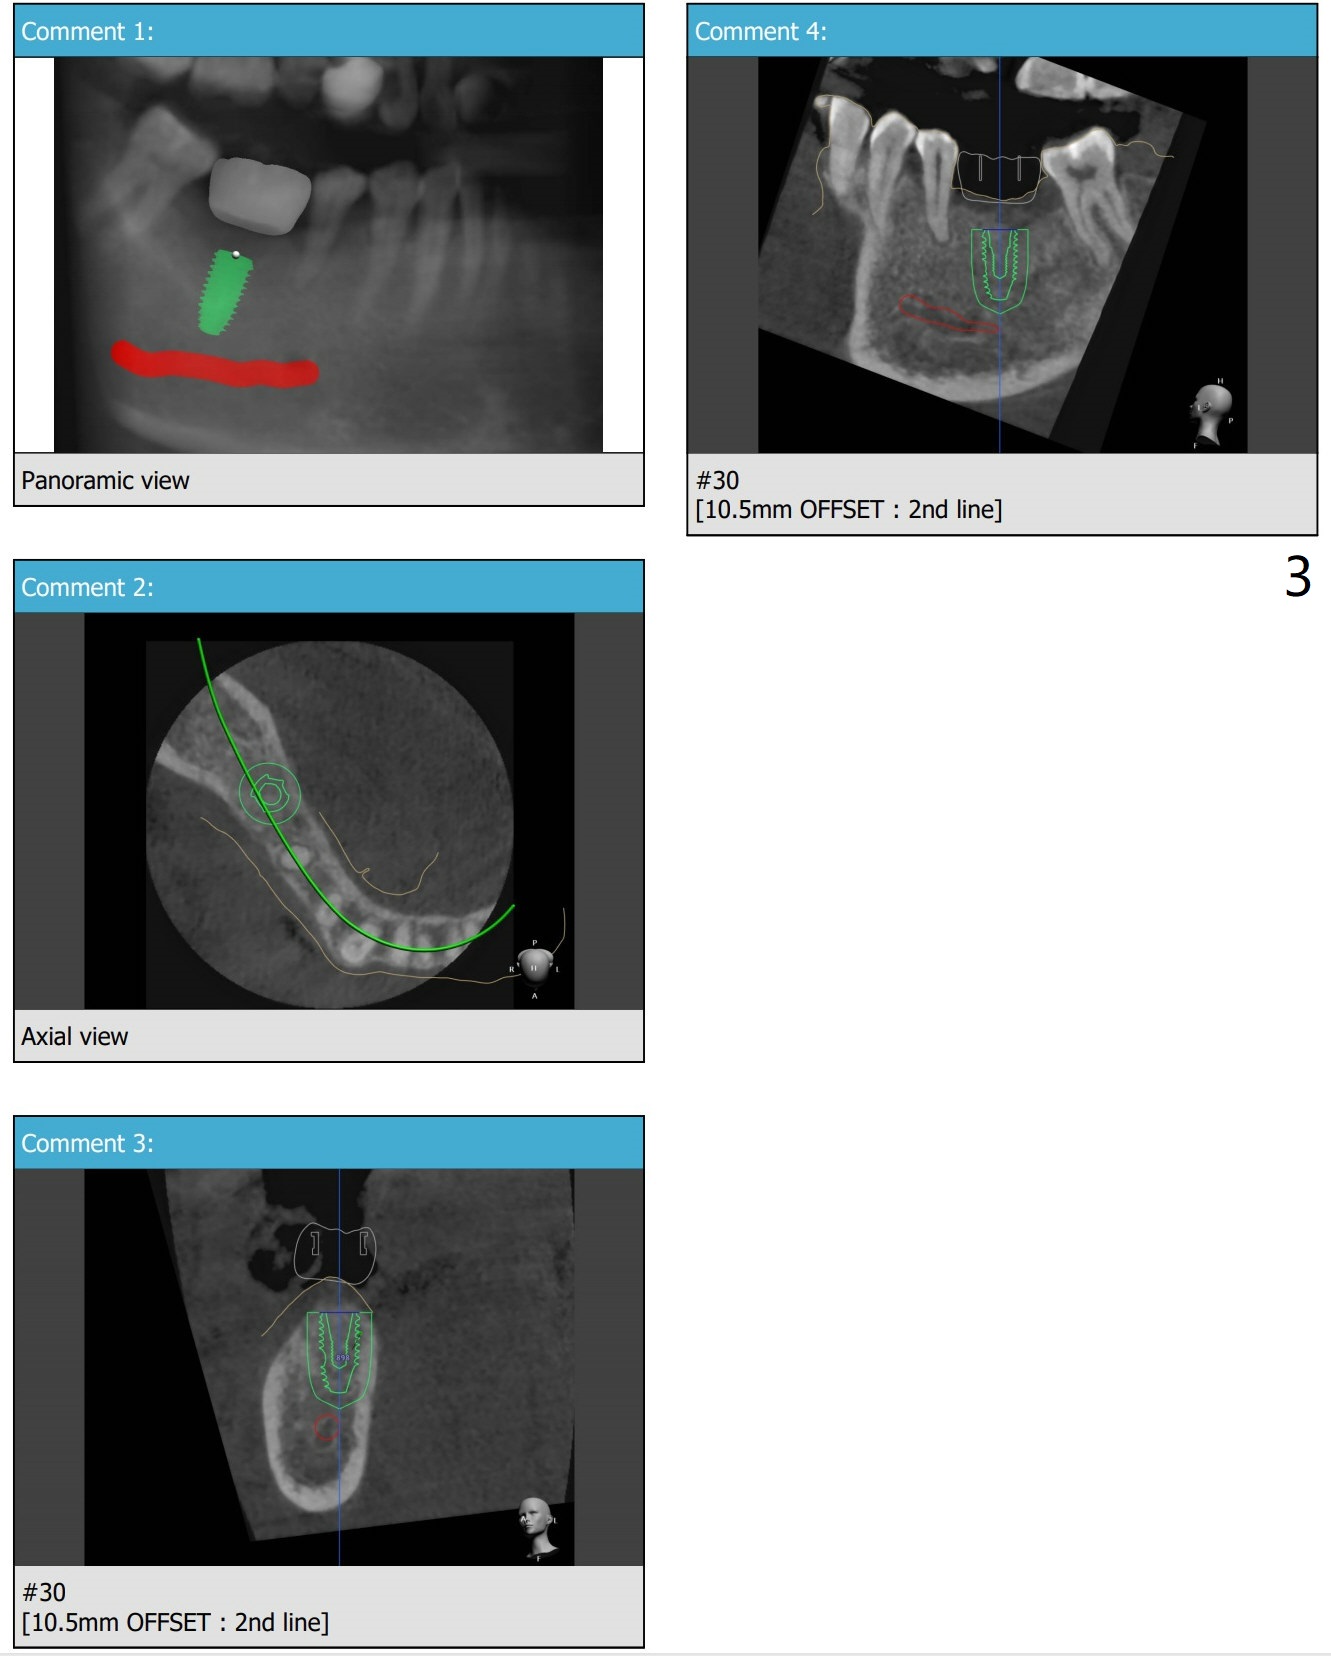

Moderate Ridge

7 months post implant removal and bone graft. Tatum screw (cylindrical) implant (prepare 4.5x14 mm dummy implant and tap). In fact IBS implant is placed instead because of nervousness of the patient.